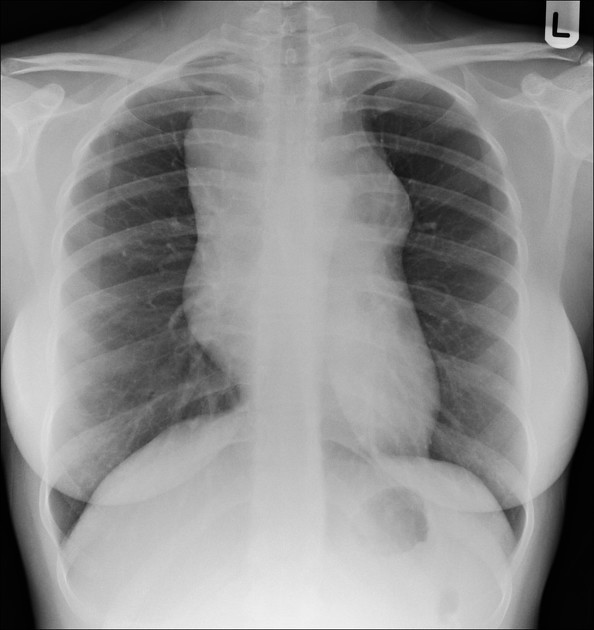

CLINICAL HISTORY:

23yo Female

SOBOE

FINDINGS:

Slight right sided volume loss with a tapering vertical curvilinear opacity in the right lung base, running parallel to the heart border.

Chest appearances are otherwise normal.

IMPRESSION:

Appearances are in keeping with scimitar syndrome.

BACKGROUND:

Scimitar syndrome represents a combination of pulmonary hypoplasia and partial anomalous pulmonary venous return. In the vast majority of cases it is right sided. It may be associated with congenital cardiac abnormalities.

DIFFERENTIAL DIAGNOSIS:

FOLLOW UP:

Cardiology referral

Consideration of further imaging with ECHO or CT